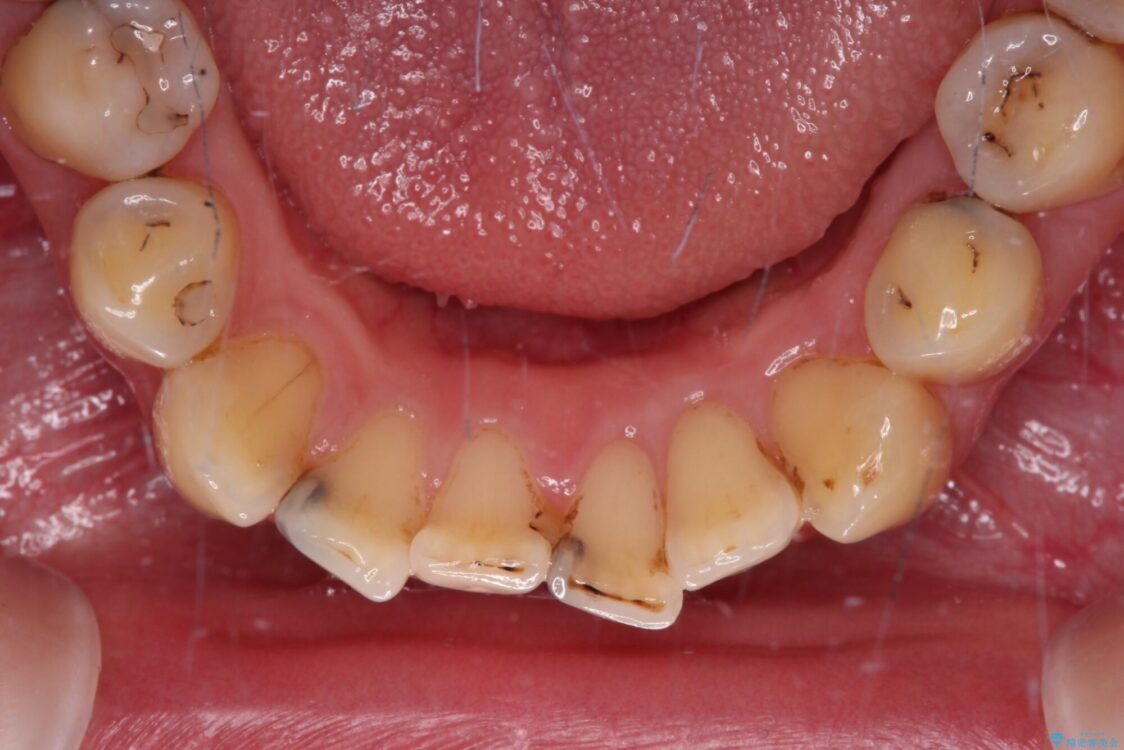

上下前歯や奥歯の虫歯治療を希望して来院された患者様です。

全顎的にむし歯が多く、根管治療の必要な奥歯や、審美的に気になっている前歯を中心にオールセラミッククラウンにて補綴治療を行うこととしました。

治療前

• むし歯だらけの前歯をオールセラミッククラウンできれいに 治療前画像